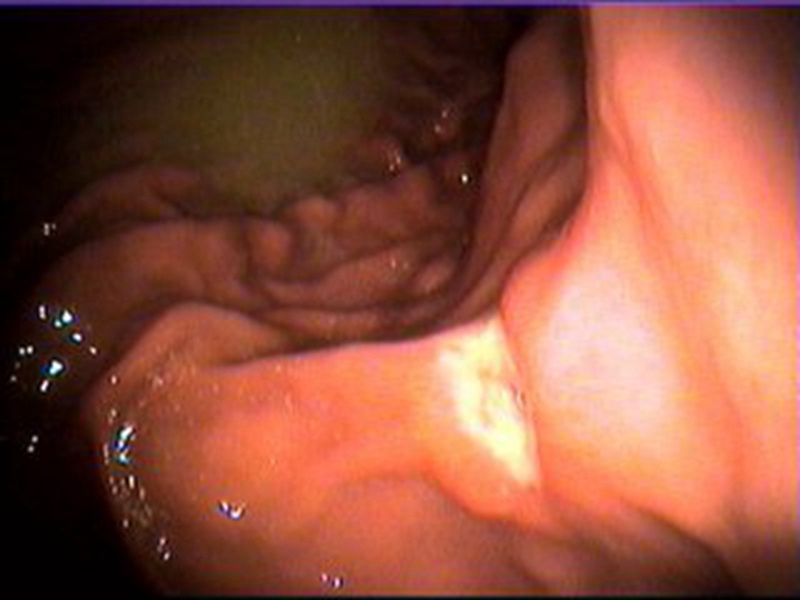

腫瘤腸腫瘤病變真